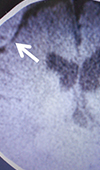

Infantile Acute Subdural Hematoma with Retinal Hemorrhage Caused by Minor Occipital Impact Witnessed by an ICU Nurse: A Case Report

An acute subdural hematoma (ASDH) in infants without external signs of trauma is differently recognized as shaken baby syndrome (SBS) or abusive head ... Read more

10.36959/595/406